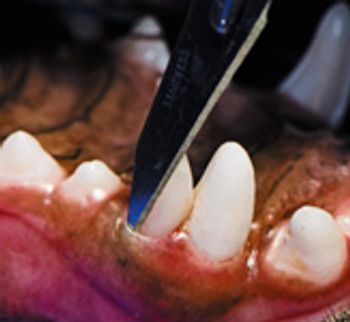

Gingival bleeding on probing indicates inflammation and requires treatment.

The degree of severity of periodontal disease relates to a single tooth; a patient may have teeth that have different stages of periodontal disease. Here is an outline of the American Veterinary Dental College-approved periodontal disease classifications.